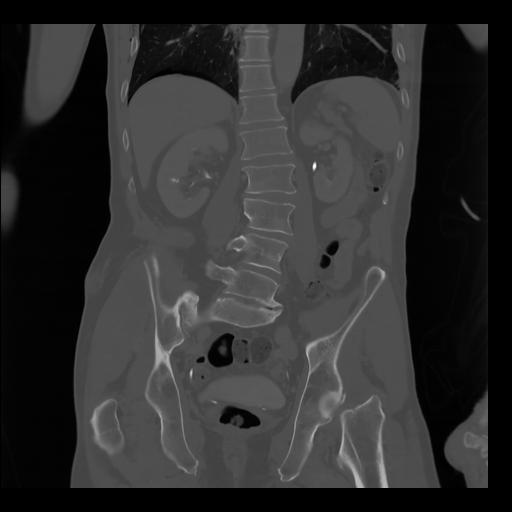

35 CUERPO,CE,Coronal,3.000,CUERPO,Coronal,